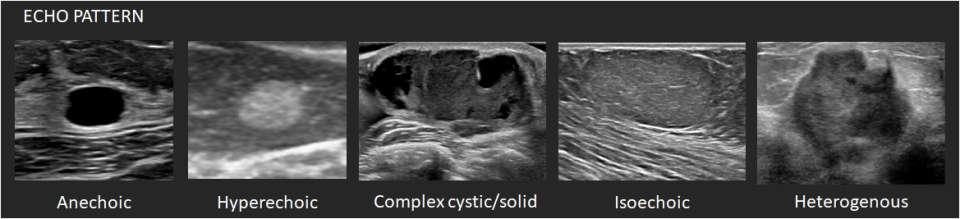

Echo pattern: The echogenicity of masses is described relative to the mammary fat.

- Anechoic – There are no internal echoes.

- Hyperechoic – There is increased echogenicity relative to fat or equal to fibroglandular tissue.

- Complex cystic/solid – There are both anechoic (fluid) and echogenic (solid) components.

- Hypoechoic – There is decreased echogenicity relative to fat.

- Isoechoic – There is the same echogenicity as subcutaneous fat.

- Heterogenous – There is a mixture of echogenic patterns within a solid mass.